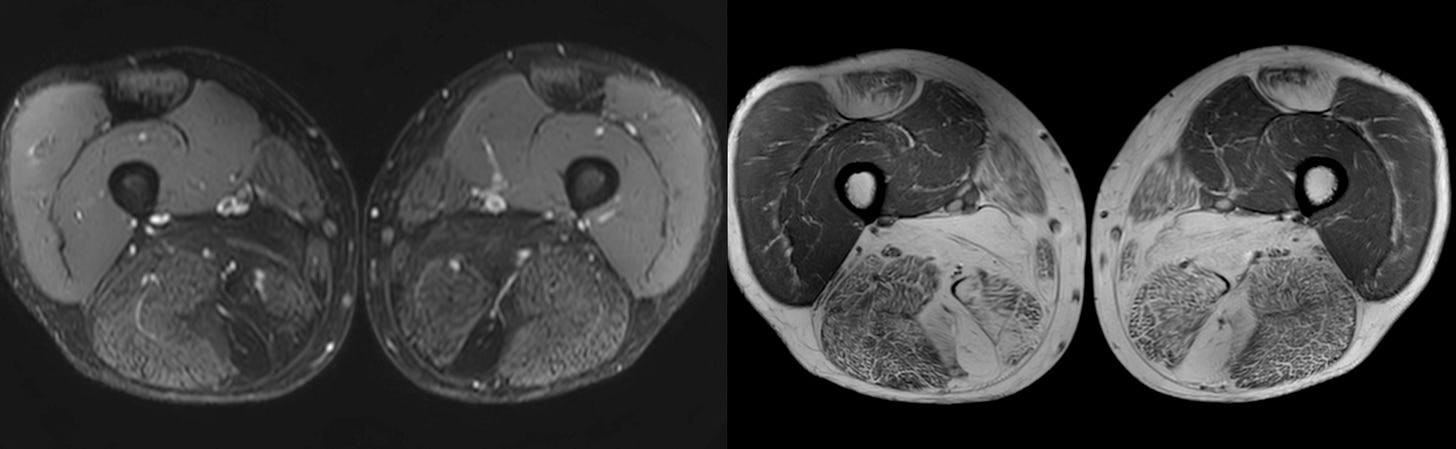

Case 63: The Honeycomb Pattern of Myositis

61-yrs old with recent diagnosis of a myopathy.

What is striking is the honeycomb pattern

The video describes the classic honeycomb pattern in this patient’s muscles and the implications and compares with the other patterns - fascial and peripheral/foggy described earlier in previous videos.